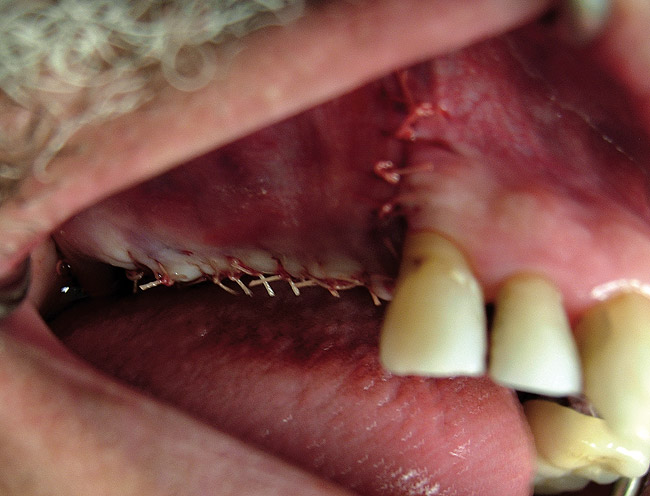

Figure  7  The graft after suturing.

Figure 7